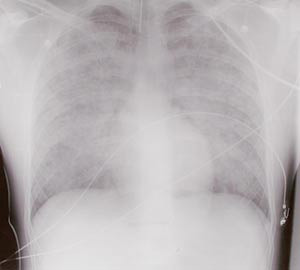

Røntgen thorax viste uttalte ulne, spredte fortetninger bilateralt (fig 1). Transøsofageal ekkokardiografi viste hyperdynamisk sirkulasjon, ingen klaffefeil og normal kontraktilitet. Tilkoblet respirator fikk han 100 % oksygen, og han ble behandlet med et høyt positivt endeekspiratorisk trykk (PEEP). På tross av dette var han alvorlig hypoksisk og hadde metabolsk acidose. Han var også hypotensiv (60/40 mm Hg), og det ble startet med væske- og vasopressorterapi. På bakgrunn av manglende behandlingsrespons ble han etter hvert snudd i mageleie. Dette bedret oksygeneringen.

Årsaken til pasientens lungeødem var en tid usikker. På bakgrunn av anamnese, undersøkelser, funn av brukerutstyr og kontakt med Giftinformasjonssentralen konkluderte vi med at det var heroinindusert. Pasienten ble gradvis bedre, og neste dag var han våken og pustet med moderat respiratorstøtte. Røntgen thorax viste betydelig tilbakegang av infiltratene. Videre ble forløpet komplisert av pneumoni og akutt lungesviktsyndrom (ARDS). Han ble ekstubert 18 dager etter innkomst og utskrevet åtte dager senere.

De vanlige symptomer og funn ved heroinoverdoser er relatert til opiateffekten slik som nedsatt bevissthet, nedsatt respirasjonsfrekvens og miotiske pupiller. Ved fullt utviklet lungeødem kan pasienten ha skummende rødt ekspektorat og være cyanotisk. Symptomer på lungeødem kommer vanligvis innen 1 – 2 timer, sjeldnere innen fire timer etter inntak. Ved mildere tilfeller kan man ofte påvise nedsatt perifer oksygenmetning til tross for normal eller økt respirasjonsfrekvens. Foreslåtte diagnosekriterier er sO₂(a) under 90 % uten tilførsel av oksygen, normal eller økt respirasjonsfrekvens, opptreden innen ett døgn etter en heroindose og røntgenologiske lungeinfiltrater uten andre kjente årsaker (4). Infiltratene er vanligvis bilaterale, spredte og ulne. Unilaterale infiltrater kan forekomme. Arteriell blodgassanalyse vil som regel vise acidose, hypoksi og varierende grad av hyperkapni. Grad av sirkulatorisk påvirkning vil variere med grad av sympatikushemning. De dårligste pasientene vil ofte ha hypotensjon med en kompensatorisk takykardi. Man vil finne et lavt sentralt venetrykk, moderat forhøyet lungearterietrykk og normal lungekapillarmotstand (8).